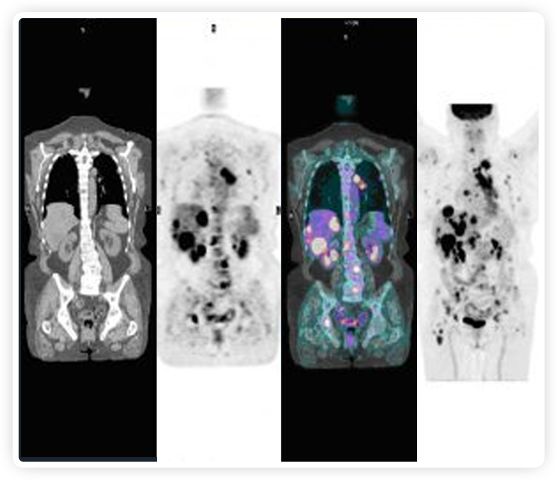

正電子發(fā)射斷層掃描(PET)是癌癥檢測中已建立的成像標(biāo)準(zhǔn),與其他成像方式相比,PET能提供高靈敏度和特異性的圖像。

到目前為止,放射腫瘤學(xué)中(使用的圖像主要是結(jié)構(gòu)性的,而PET圖像可以提供生物學(xué)信息。通過使用注射示蹤劑,例如18-FDG,PET可以描繪腫瘤的代謝活性,使其“點亮”。(FDG是用于可視化癌癥代謝的最廣泛使用的示蹤劑。與正常組織相比,腫瘤細胞保留更高水平的FDG。)不同的PET示蹤劑可以識別腫瘤的不同生物學(xué)特征,例如特定生物標(biāo)志物抗原(例如,PSMA)或甚至探測免疫系統(tǒng)本身(例如,PDL1表達或活化的T細胞)。

PET+放療共同治療

RefleXion將PET成像與立體定向放射治療相結(jié)合。在注射示蹤劑后,RefleXion的技術(shù)基于示蹤劑信號實時地在一個或多個目標(biāo)上引導(dǎo)治療性X射線。使用這種專有方法,RefleXion的平臺有可能比現(xiàn)有系統(tǒng)向癌癥病變提供更高劑量的輻射,并改善周圍健康組織的保護。

為了避免PET長圖像采集時間,RefleXion開發(fā)了一項專利技術(shù)使用重合的PET光子對來指導(dǎo)放射治療束,因為實時檢測發(fā)射的光子,為生物指導(dǎo)提供了一種時間有效的方法。